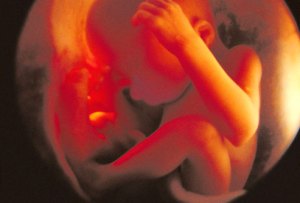

Fetus at 4 Weeks

Fetus at 8 Weeks

Fetus at 12 Weeks

Fetus at 16 Weeks

Fetus at 20 Weeks

Fetus at 24 Weeks

Fetus at 28 Weeks

Fetus at Week 36

All pictures came from:  http://www.webmd.com/baby/slideshow-fetal-development